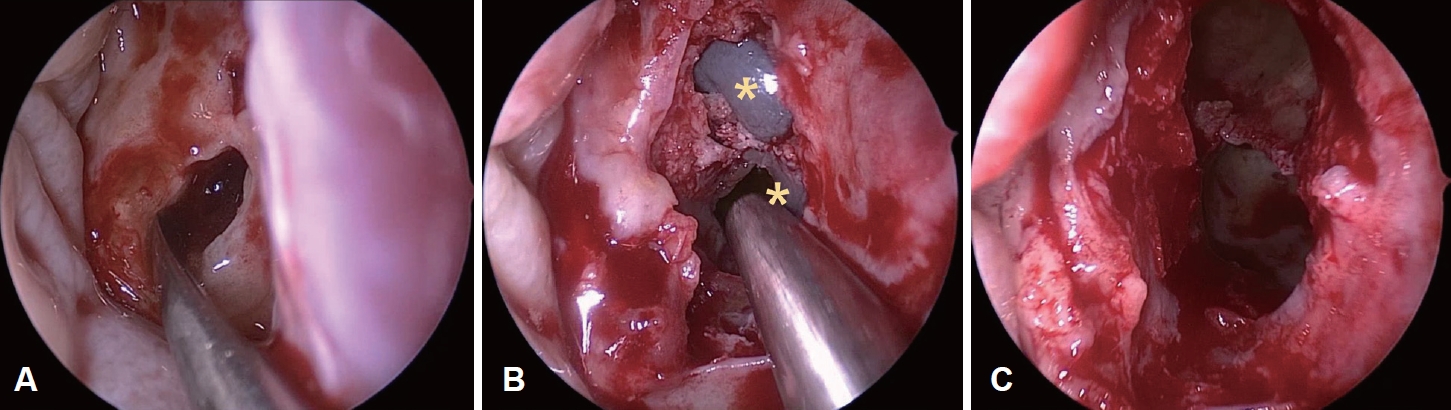

이에 점액낭종을 동반한 좌측 사골동 섬유 이형성증으로 진단하였고, 임상증상이 병변의 위치와 상관 관계가 일치하고 점액낭종이 동반되어 있기에 부비동 내시경을 이용한 수술을 계획하여 시행하였다. 전신마취하 내시경 검진 후 좌측 섬유이형성증 감량술, 점액낭종 조대술 및 좌측 중비도 상악동개방술(middle meatal antrostomy)을 시행하였다. 특징적인 소견으로 프리어 엘리베이터(freer elevator), 절단 겸자(cutting forceps)로 병변의 전방 격막을 제거하자 한차례 점액낭종이 조대되었고 이어 미세절삭기(debrider)로 후상방에 위치한 두 번째 점액낭종의 조대술을 시행하였다. 그 내부에는 갈색의 점액성 분비물이 가득 차 있었다(Fig. 3).

NotesAuthor Contribution Conceptualization: Seung Heon Kang, Hyun Jik Kim. Data curation: Seung Heon Kang, Hyunkyung Cha, Seung Cheol Han. Formal analysis: Seung Heon Kang, Hyun Jik Kim. Funding acquisition: Seung Heon Kang. Investigation: Seung Heon Kang. Methodology: Seung Heon Kang. Project administration: Seung Heon Kang. Resources: Seung Heon Kang. Supervision: Hyun Jik Kim. Validation: Seung Heon Kang. Visualization: Seung Heon Kang. Writing—original draft: Seung Heon Kang. Writing—review & editing: Seung Heon Kang. Fig. 1.Endoscopic finding of expansile extruding mass covered with normal mucosa in left middle meatus. Fig. 2.Left ethmoid fibrous dysplasia combined with mucocele (A) eroded lamina papyracea (B) involvement of pterygoid plates (C) hypoplastic left maxillary sinus and right septal deviation. Fig. 3.Endoscopic findings of operation (A) brownish content spilled out from the mucocele (B) visualization of septated mucoceles (asterisks) after removal of anterior wall of fibrous dysplasia (C) after marsupialization. Fig. 4.Histopathologic findings of FD, pathologic report of FD: osteoid trabeculae that are narrow, curvilinear or irregularly-shaped are arranged haphazardly in a background of dense fibroblastic stroma (hematoxylin and eosin, original magnification ×20). FD: fibrous dysplasia. REFERENCES1. Weinstein LS, Shenker A, Gejman PV, Merino MJ, Friedman E, Spiegel AM. Activating mutations of the stimulatory G protein in the McCune-Albright syndrome. N Engl J Med 1991;325(24):1688-95.